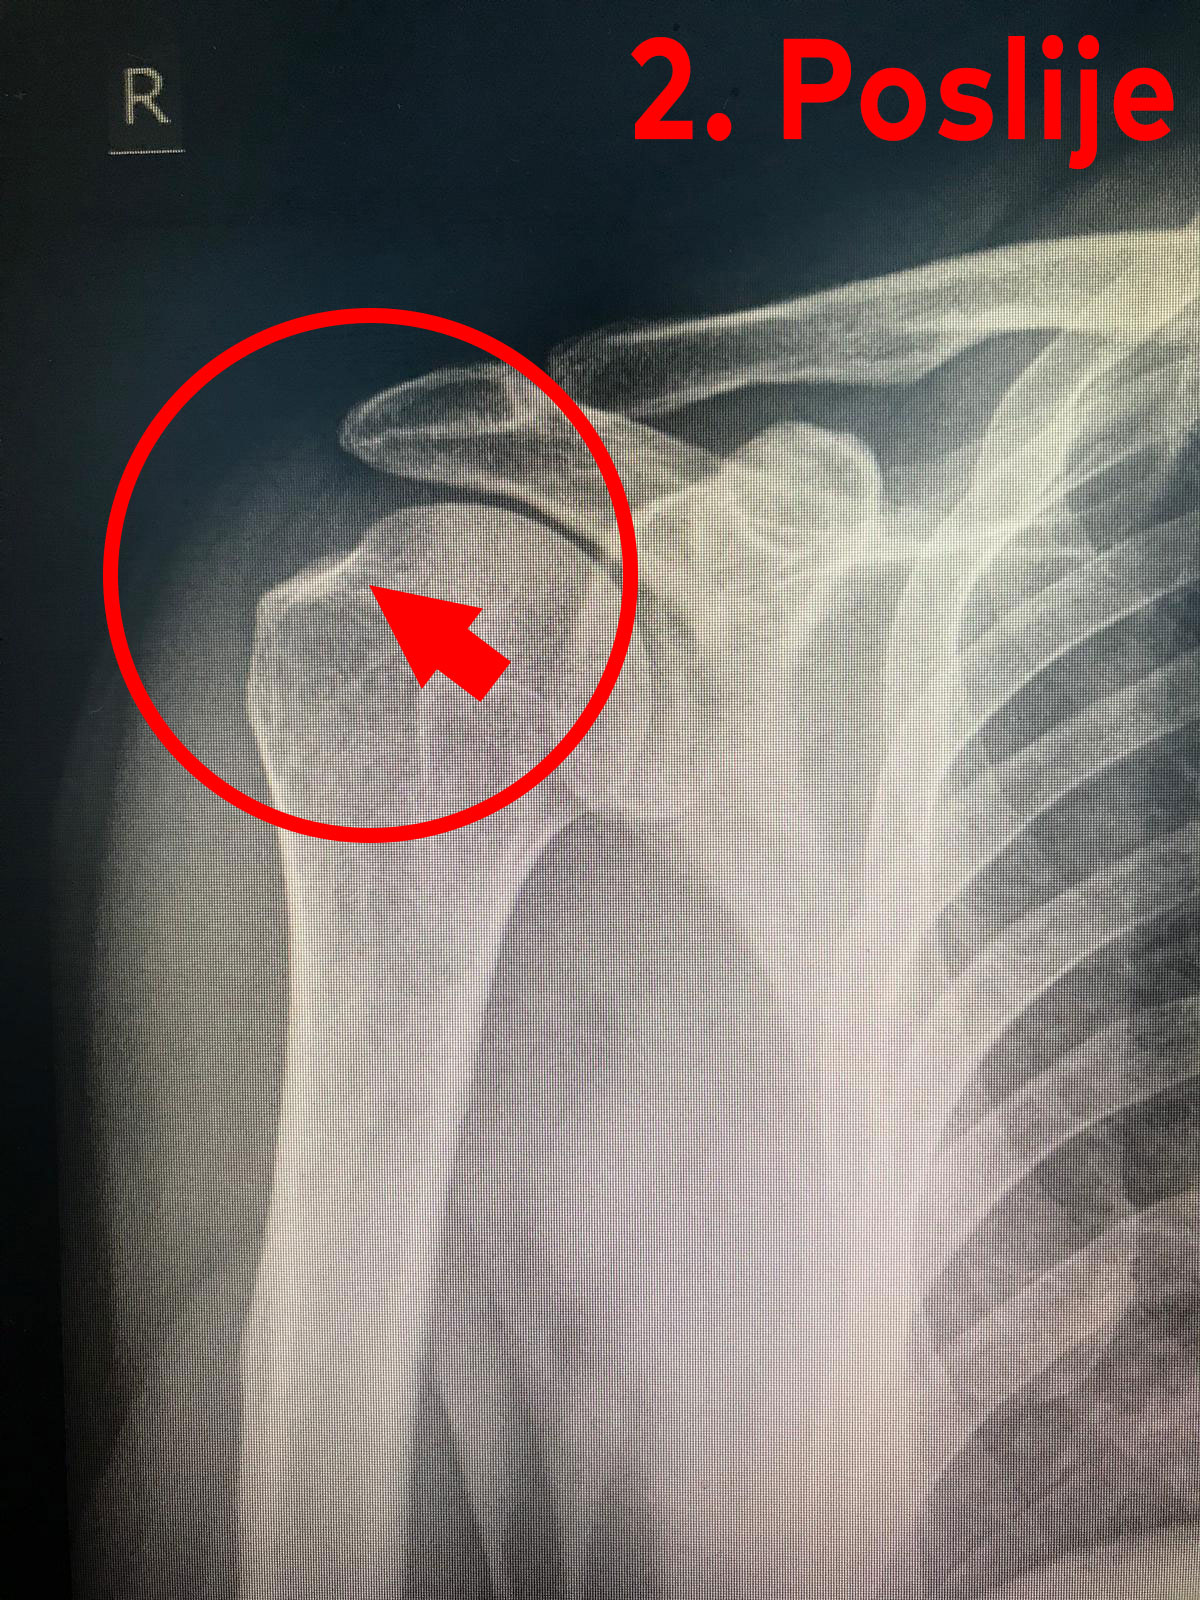

Na slici broj 1 prikazan je slučaj kalcifikata u ramenu prije dolaska na terapiju. Dok je na slici broj 2 prikazan rezultat naše uspješno provedene fizikalne terapije.

Liječenje: cilj je smanjiti bol u ramenu i ubrzati proces razgradnje (resorpcije) kalcifikata.

U akutnoj fazi se daju NSAR, a potom počinje fizikalna terapija. Od fizikalnih procedura mi koristimo: UZ terapiju, iontoforezu, interferentne struje, bioptron lampu, krioterapiju i manualne tehnike kao i vježbe (prvo pendularne, pasivne, aktivnopotpomognute i na kraju aktivne – cilj vježbi je spriječiti kontrakturu ramena).

Ukoliko fizikalna terapija ne daje dobre rezultate, kalcifikat se može odstraniti kirurški i to: prvi način je artroskopija ramena (gdje je brži postoperativni oporavak zbog malih ulaznih rana), a drugi način je operacija na otvorenom ramenu, poslije koje je oporavak znatno duži nego kod artroskopije.